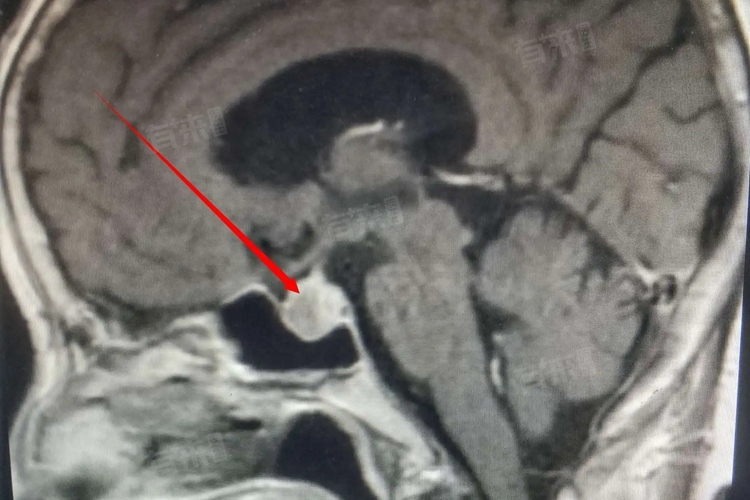

脑垂体疾病如垂体瘤、垂体功能减退等,会影响其正常分泌功能,导致一系列内分泌紊乱症状。诊断脑垂体疾病通常需结合血液激素水平检测、影像学检查(如MRI)等手段,治疗方法包括药物治疗、手术切除及放射治疗等。

- 对于有家族遗传病史、既往头部外伤史或肿瘤病史的人群,定期进行垂体相关激素检测和头颅MRI检查,有助于早期发现潜在病变。

- 确诊脑垂体疾病后,严格遵循医嘱治疗。如垂体瘤患者需根据肿瘤类型、大小及激素分泌情况,选择合适的治疗方案,术后或放疗后定期复查,监测激素水平和垂体功能恢复情况。